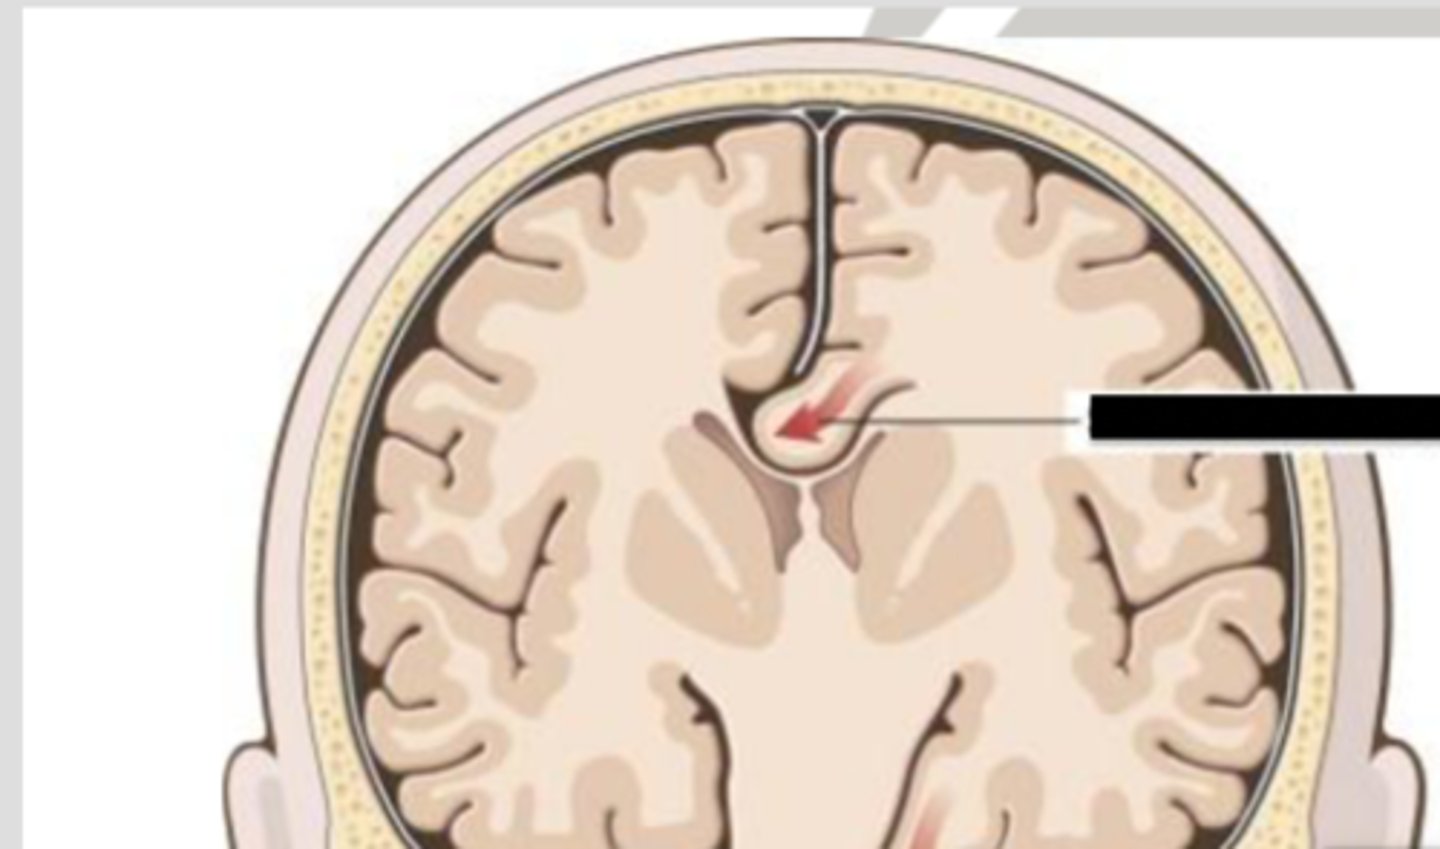

subfalcine (cingulate) herniation

herniation of the brain where the medial frontal lobe shifts under the falx cerebri

transtentorial (uncal) herniation

herniation of the brain where the temporal lobe shifts through the tentorial notch

*1 on diagram